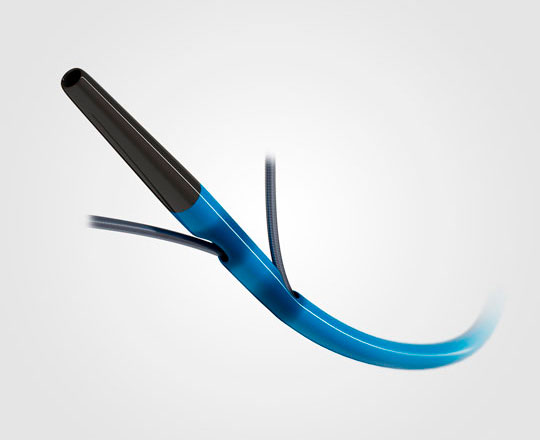

True Flow (Bard, EEUU) es un balón de valvuloplastia que permite el flujo a su través mientras está inflado. Su recubrimiento exterior está compuesto por un tejido de fibras que evita el deslizamiento del balón al abrirse sobre los velos valvulares, por lo que no se necesita estimular el corazón con marcapasos. Este tejido esta formado por poliuretano de alto peso molecular, poliéster y fibras de aramida (componente estructural del Kevlar) que posee una baja distensibilidad y alta resistencia a la rotura. El interior del balón tiene 8 globos de pequeño diámetro en el perímetro del balón principal, y deja un espacio entre ellos por donde fluye la sangre. El dispositivo mide 3,5 cm de largo y está disponible en seis tamaños, con diámetros que van de los 18 a los 26 mm. Los más pequeños son compatibles con un introductor de 11 French y el más grande con introductor de 16 French.